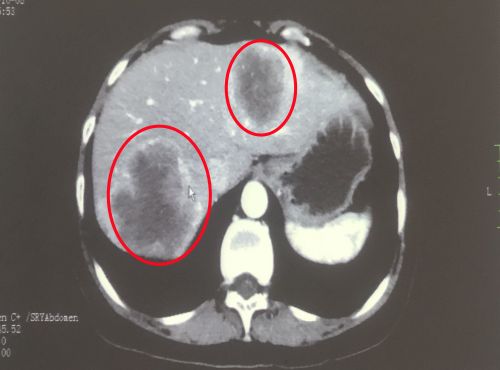

治疗前影像显示:肝脏有多发转移灶(红圈内)。

长沙43岁的林女士近半年来反复腹痛、大便带血,每次想上大号却又解不出什么,以为是痔疮发作没当回事。当她因体检发现“肝脏占位”到湖南省人民医院肝胆外科住院时,却被告知:肝脏上的多发肿块是结肠癌转移所致。

经湖南省人民医院结直肠肿瘤多学科团队专家讨论后,林女士在接受化疗+靶向药物治疗后,肿块明显缩小,再由结直肠肛门外科肖志刚主任团队和肝胆外科成伟教授团队为其施行结肠及肝脏肿瘤同期切除手术。切下的结肠肿瘤约有成人拳头大,切除的肝脏及肿瘤约占全肝的30%。